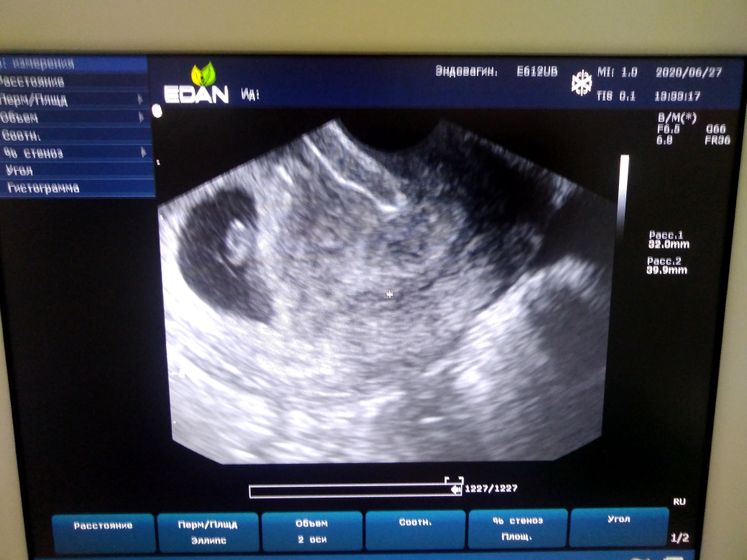

По узи нам 6,5-6,6 недель… По мес 7,3… Видимо овуляция была чуть позже, так как цикл длиннее среднего (31-33дня) Вздохнула с облегчением…

Ну и наше первое фото